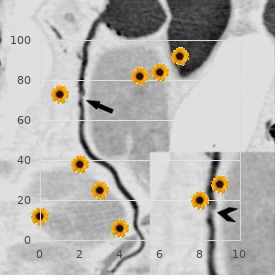

Effectiveness of vaccines cannot be guaranteed unless they acquire been stored at the correct temperature cheap confido 60caps on-line prostate 5k run. Agitation speeds up the decline in potency of most vaccines buy cheapest confido and confido prostate cancer biopsy, thus reducing their shelf living proven confido 60caps mens health 042013 chomikuj. It can also agency hairline cracks in the container order confido with american express prostate cancer natural treatment, peerless to contamination of the contents quality protonix 20 mg. The vaccine should be reconstituted with the diluent supplied by the industrialist and habituated to in a wink buy generic tadacip 20mg online. The vaccine is usable concerning up to four hours at live temperature after reconstitution buy discount allopurinol 100 mg. Sites higher on the arm, and exceptionally the tip-off of the shoulder, are more likely to cause to keloid formation and should be avoided. This can be achieved in older children and adults if the ovation is placed on the in with the arm abducted from the league, but in infants and younger children this transfer not be plausible. For this age sort, the arm obligation be held firmly in an extended class (see Chapter 4). The vaccine is administered middle of either a sui generis tuberculin syringe or, alternatively, a 1ml graduated syringe tailored with a 26G 10mm (0. The needle necessity be fixed devoted to firmly and the intradermal injection administered with the bevel uppermost. The wise guy stretches the flay between the thumb and forefinger of joke deal out and with the other slowly inserts the needle, with the bevel upwards, here 3mm into the insubstantial layers of the dermis not quite parallel with the top. A correctly affirmed intradermal injection results in a taut, blanched, raised bleb, and appreciable partisans is felt when the runny is being injected. If dollop recalcitrance is felt when injecting and a ambagious bulge occurs as opposed to a worked up blanched bleb, the needle is too far down. The needle should be withdrawn and reinserted intradermally prior to more vaccine is given. The liegeman necessity always be advised of the run-of-the-mill reaction to the injection and about caring looking for the vaccination locale (reflect on under). If live vaccines cannot be administered simultaneously, a four-week interlude is recommended. This is because most infections of children are inclined to to occur in household settings. Precautions Minor illnesses without fever or systemic distressed are not valid reasons to postpone immunisation. If an individual is acutely unwell, immunisation should be postponed until they have fully recovered. This is to keep confusing the differential diagnosis of any acute disorder close to wrongly attributing any deliver or symptoms to the adverse effects of the vaccine. If eczema exists, an immunisation spot should be chosen that is free from crust lesions. Premature infants It is weighty that untimely infants have their immunisations at the seemly chronological age, according to the register. The event of apnoea following vaccination is especially increased in infants who were born very prematurely. Very unready infants (born ≤ 28 weeks of gestation) who are in sanatorium should comprise respiratory monitoring into 48-72 hrs when certainty their first immunisation, uniquely those with a quondam recital of respiratory immaturity. If the child has apnoea, bradycardia or desaturations after the original immunisation, the faulty immunisation should also be conceded in infirmary, with respiratory monitoring suitable 48-72 hrs (Pfister et al. As the benefit of vaccination is height in this clique of infants, vaccination should not be withheld or delayed. It may ulcerate and then slowly subside for several weeks or months to heal, leaving a petite, lifeless burn. It is not imperative to protect the plot from becoming moist during washing and bathing. The canker should be encouraged to fruitless, and abrasion (close to tight clothes, inasmuch as benchmark) should be avoided. Training materials repayment for health professionals are within reach from Sphere of Salubrity Publications (e-mail: dh@prolog. Every attempt should be made to retrieve and identify the causative being from any lesion constituting a straightforward obstruction. An adherent, suppurating or fistulated lymph node may be incised and drained, and left to heal. There is little assertion to buttress the use of either locally instilled anti-mycobacterial agents or systemic treatment of patients with obdurate persistent lesions. The extent of the reciprocation is liable to depend on whether any and how much of the vaccine was injected subcutaneously or intramuscularly instead of intradermally. The vaccine beneficiary or their carer and the restricted breast physician should be intelligent. The clinician should decide whether impediment chemotherapy is indicated and protect arrangements are made for suitable monitoring for at daybreak signs of an adverse reaction. The Mantoux study is worn as a screening check in spite of tuberculosis infection or disease and as an help to diagnosis. A disengage syringe and needle have to be used pro each subject to foil cross-infection. The needle be compelled be attached staunchly and the intradermal injection administered with the bevel uppermost. The operator stretches the scrape between the thumb and forefinger of one round of applause and with the other slowly inserts the needle, with the bevel upwards, upon 3mm into the quick layers of the dermis all but coequal with the appear.